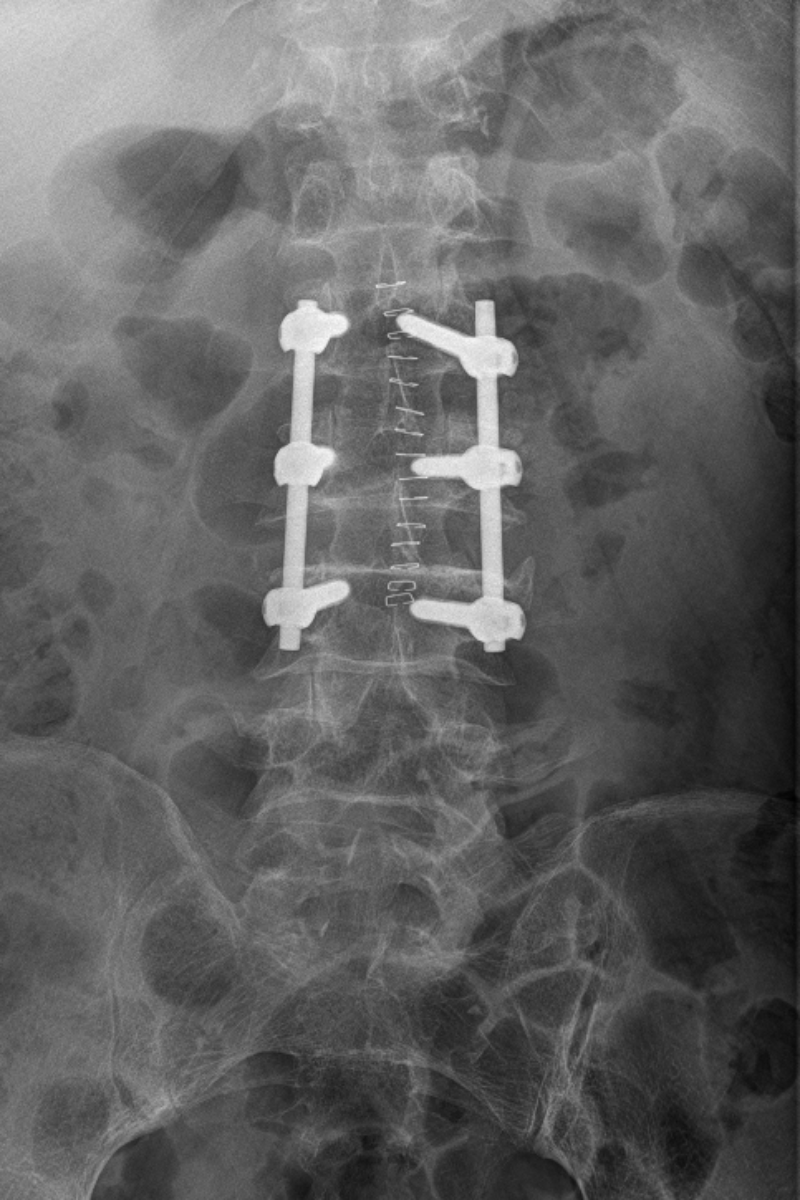

60歲的廖叔,因不小心跌倒,致腰背部疼痛、活動受限,在家自己吃止痛藥、休息后仍感腰背部疼痛難忍,萬般無奈之下,到我院就診,門診行腰椎CT檢查明確為腰2椎體壓縮性骨折,后便安排住進了脊柱外科。患者平時有高血壓病、心律不齊,長期服藥質量,對于手術抱有疑慮,感覺手術風險相當大,住院后姚仕奮及其團隊對廖叔完善相關檢查,評估其身體狀況還可以,并沒有手術禁忌癥,姚仕奮與廖叔及其家人進行了詳細的溝通,告訴他手術創傷并不大,做完手術在支具保護下第二天即可下地活動,廖叔及其家里人了解病情后,決定手術治療。

姚仕奮及其團隊與麻醉科主任孫岸靈團隊為廖叔完善術前準備,在麻醉團隊的保駕護航下,于2023年10月20日為廖叔完成了腰2椎體壓縮性骨折后路切開釘棒系統復位內固定術+植骨術,1小時內便完成了手術,術后護士長龍婷帶領團隊為廖叔制定了詳盡的護理方案,指導廖叔康復鍛煉。術后第2天,廖叔在脊柱外科醫護人員的指導下,已可自行下地活動,恢復十分良好,于11月3日順利出院。

這是脊柱外科開科以來的第一臺手術,也是脊柱外科的常規手術之一。每年都有大量外傷患者胸腰椎骨折需行手術治療,脊柱外科的開科,專科化的技術,能更精準、高效的為此類患者進行手術診治。